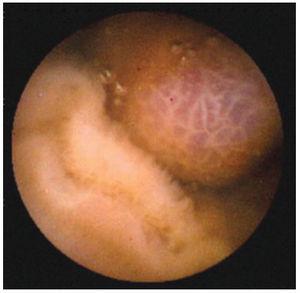

En todos los casos se administró la cápsula PillCam® de Given Imaging M2A. Se dio a deglutir con agua. Se utilizó un equipo de recuperación de imágenes que consta de nueve antenas receptoras, colocadas en todos los cuadrantes del abdomen, con un tiempo de grabación promedio de ocho horas. Al finalizar el estudio, se decodi- ficaron las imágenes en un programa diseñado para su lectura en computadora [Rapid Reader®] (figura 1). Los estudios fueron interpretados, cada uno en promedio de dos horas por los autores, que cuentan con experiencia en endoscopia, así como entrenamiento en la revisión de imágenes de cápsula endoscópica, apoyados por un atlas elaborado por expertos en estudios de cápsula endoscópica. Se registraron los hallazgos de todos y cada uno de los pacientes, emitiendo un reporte final por escrito, del cual se conservó una copia. Cabe mencionar que no hubo dificultades técnicas con el manejo de las imágenes. Para el estudio se realizó una hoja de captación de datos, donde quedaron registrados el número progresivo de estudio, iniciales del paciente, sexo, edad, motivo de envío y resultado del estudio de cápsula endoscópica. No se consignaron los recursos consumidos previamente por los pacientes (endoscopias, colonoscopias, internamientos, transfusiones, etc.), ya que en algunos casos acudían al estudio sin reportes previos.

Figura 1. Imagen normal. Vellosidades intestinales.